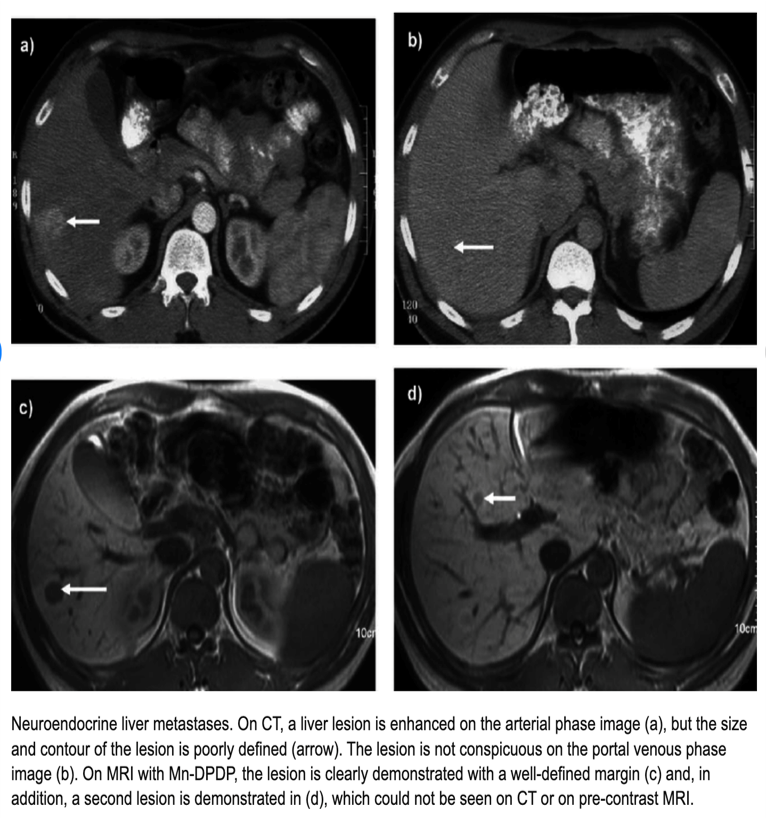

Axial CT of the abdomen showing multiple liver metastases.

Target appearance

Computed tomography (CT) scan performed in April 2016 shows three liver lesions (LLs) in arterial phase. a. The arrow indicates LL (diameter: 7 mm) with contrast enhancement suspected of metastasis at 4th segment.